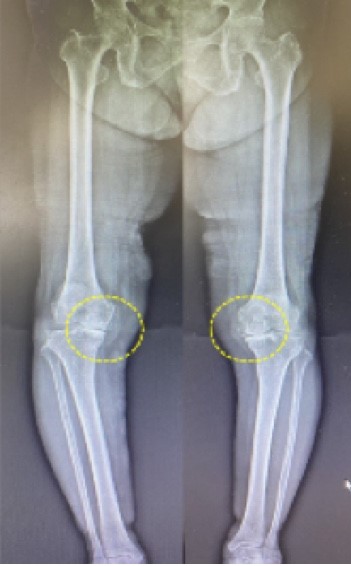

ほとんどの方が整形外科を受診し、レントゲン写真を撮り、上の写真のように膝の内側(日本人には少ないですが外側の場合もあります。)の「関節の隙間が狭くなっている」「軟骨がすり減っている」「半月板が傷んでいる」等で「変形性膝関節症」と診断名が付きます。そしてそれが膝の痛みの原因だとされる訳です。しかし実際の臨床現場においては「痛みの原因が膝関節以外にある」症例の方が多いのです。この事実に着目して当院の膝痛専科では整形外科や他の治療院とは違う視点で独自の施術を行い、「変形性膝関節症」と診断された方であっても非常に良好な改善結果を得られています。